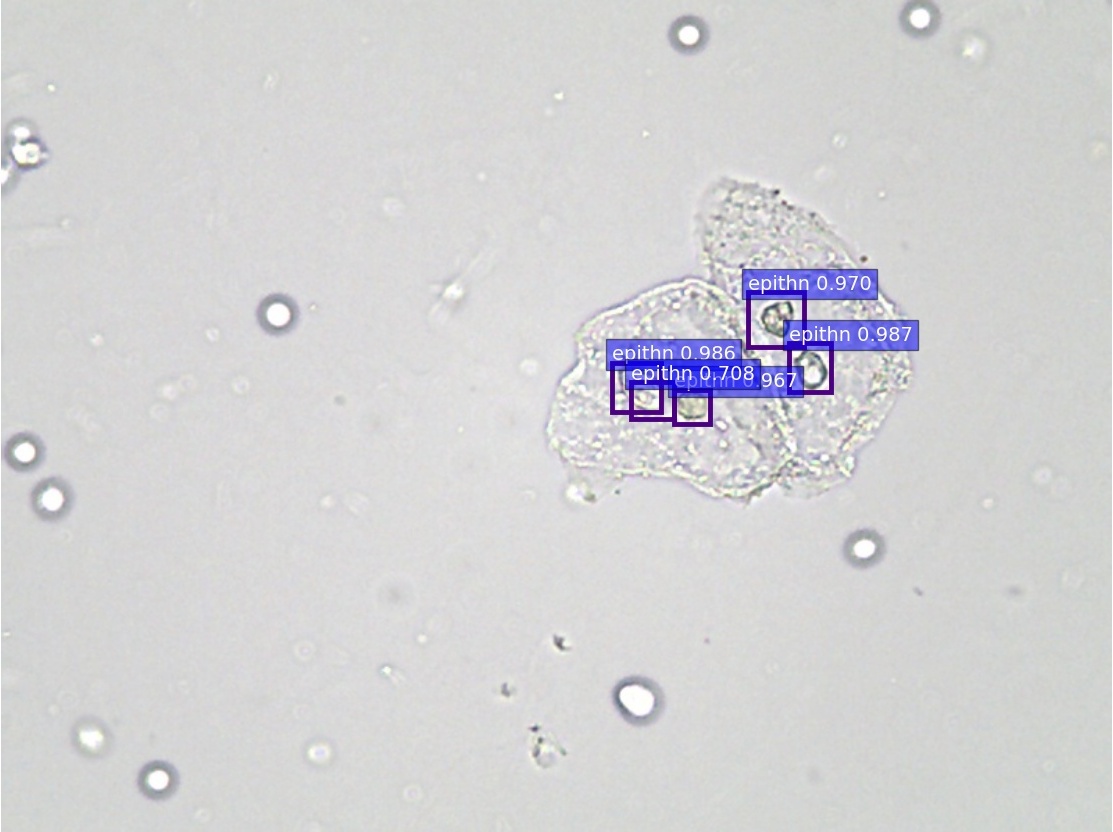

(a) annotations

Refer to caption

(b) ZF

(c) VGG-16

(d) ResNet-50

(e) PVANet

(f) SSD300

\Romannum5 : detection results of epithelial nuclei

Figure 8: Selected detection examples of urine particles on urinalysis test set. We show detections with scores higher than 0.7. All examples are divided into 7 groups, where 5 groups are at high-power field (i.e., erythrocyte, leukocyte, crystal, mycete, epithelial nuclei ) and the other 2 groups at low-power field (i.e., epithelial cell, cast ). In each group: (a) shows original image with ground truth boxes; (b-d) are Faster R-CNN detections separately on ZF, VGG-16 and ResNet-50 networks with a anchor scales of {322,642,1282,2562,5122}superscript322superscript642superscript1282superscript2562superscript5122\{32^{2},~{}64^{2},~{}128^{2},~{}256^{2},~{}512^{2}\}; (e) shows detection results on PVANet; (f) shows detection results on SSD300 model. For the ground truths and detection boxes, different categories use only different colors: eryth (red), leuko (black), epith (green), crystal (magenta), cast (cyan), mycete (yellow). As shown in this figure, the performance of SSD is inferior to Faster R-CNN, and it misses a lot of small objects.